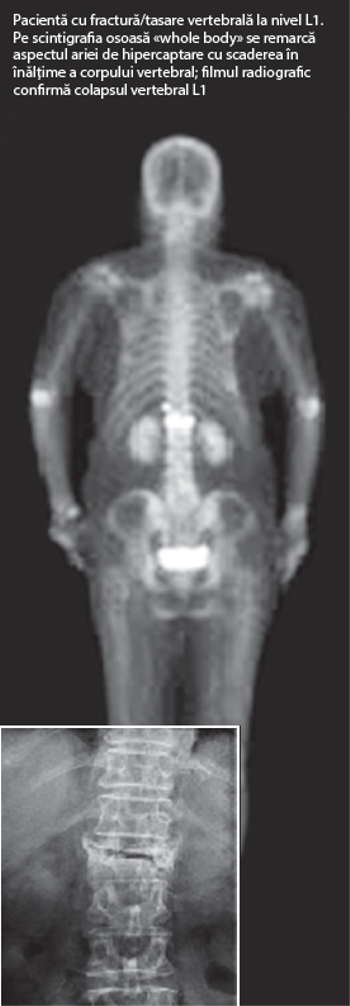

Examinarea scintigrafică se realizează la circa 2-4 ore după administrarea intravenoasă a radiofarmaceuticului, de obicei un bifosfonat marcat cu Tc99m. Achiziţia de imagini durează circa 15 minute şi ne permite evaluarea întregului schelet, atât pentru evidenţierea prezenţei unor metastaze osoase dar şi a altor patologii potenţial fragilizante cum ar fi maladia Paget mono/poliostică. Fracturile- tasări vertebrale au un aspect patognomonic pe examinarea scintigrafică, corpul vertebral având înălţime redusă şi o hiperfixare liniară a radiotrasorului.

Modificările scintigrafice (leziuni de fractură/fracturi vertebrale) vor fi coroborate cu aspectul lezional morfologic vertebral (dat de examinarile RX/IRM), permiţând astfel medicului curant să stabilească cele mai bune opţiuni terapeutice pentru pacient.